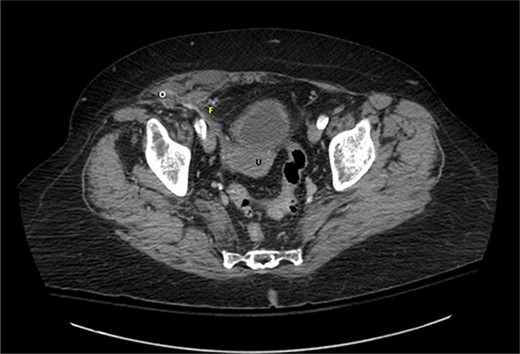

A 76-year-old Caucasian female presented to the emergency department for evaluation of 3 days of progressively worsening abdominal pain. The pain was characterized as an ache, originated in the right lower quadrant and radiated to the bilateral upper quadrants. Past medical history was significant for obesity (BMI 31 kg/m2), chronic obstructive pulmonary disease, gastroesophageal reflux disease, hypertension, hypothyroidism, heart failure with preserved ejection fraction, atrial fibrillation, and scleroderma. Pertinent surgical history included a dual-chamber pacemaker and tubal ligation. She was anticoagulated with apixaban. Physical examination revealed right lower quadrant tenderness to palpation and rebound tenderness without a palpable abdominal bulge. Contrast-enhanced computed tomography of the abdomen and pelvis did not clearly demonstrate the appendix, but rather a ventral hernia in the lower right quadrant. The fascial defect was lateral to the rectus abdominis, superior to the inguinal ligament, and inferior to the arcuate line. The defect measured 3.6 × 2.0 cm and involved the transversus abdominis and internal oblique muscle aponeuroses while the external oblique remained intact, consistent with Spigelian hernia (Fig. 1). There was an oblong structure extending parauterine into the hernia sac with a small amount of free fluid suggestive of the right ovary and fallopian tube (Fig. 2). Considering these findings and appropriate cessation of anticoagulation, the patient was taken for diagnostic laparoscopy and transabdominal preperitoneal hernia repair.

Sagittal view of contrast-enhanced computed tomography of the abdomen and pelvis demonstrating the right fallopian tube (F) attached to the uterus (U) extending into the Spigelian hernia defect containing the right ovary (O).